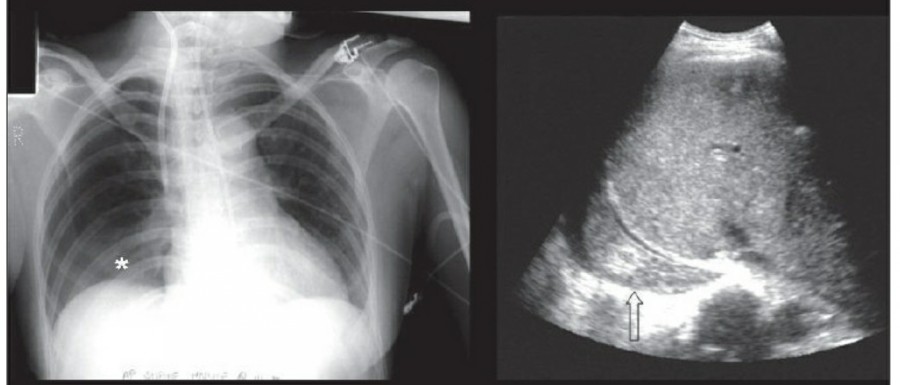

방사선 소견상 Pleural effusion은 환자 흉부의 dependent area에 고인다. Erect position에서 확인하기가 쉬운데, 폐의 base에 고임으로써 costophrenic angle blunting을 보이고 lower lobe vessel들의 흐리게 한다. Supine position에서는 확인이 더 어려운데, pleural fluid는 posterior basilar space에 고여서 폐 base 쪽으로 intensity가 증가하는 homogenous density를 보인다. 정상적인 bronchoalveolar marking은 이와 같은 veil-like density 안에서 확인 가능하다. Fluid 양이 늘어나면서 diaphragm의 윤곽이 흐릿해지고 costophrenic angle도 없어지는데, 이 costophrenic angle blunting이 없더라도 pleural space에 1L 정도의 pleural fluid가 있을 수 있다는 것을 기억해야 한다. 그 양이 더욱 늘어날 수록 fluid는 lung의 apex에서 pleural cap으로 나타날 수 있으며, 이는 supine position에서도 확인 가능하다. Pleural fluid는 lung의 medial side에 고일 수도 있으며 이는 mediastinum의 확장으로 보일 수도 있다.

적은 양의 pleural fluid는 꼼꼼히 확인하더라도 supine radiograph에서 놓칠 수 있는데, 만약 chest X ray에서 보이지 않지만 임상적으로 의심이 되는 경우에는 lateral decubitus film으로 확인해 볼 수 있다. Fluid는 dependent position에 고이므로 환자를 의심되는 방향으로 옆으로 눕혀야 한다. Lateral decubitus film은 적은 양의 pleural fluiid는 물론이고 loculated effusion과 free effusion을 확진하는 데도 도움이 된다. 특히 loculated effusion은 한 개 이상의 drain이 필요할 수 있으므로 pleural drainage를 고려할 때 특히 중요한 검사이다. 중환자에서 흔하게 나타나는 subplumonic effusion은 lung base에 존재하는 pleural effusion을 말하는데, chest X ray 상에서 raised hemidiaphragm with flattening and lateral displacement of the dome 형태로 나타나며, lateral decubitus film이 도움이 된다.

Loculated pleural effusion의 진단은 쉽지 않은데, 특히 fissure 안에 있을 때 어렵다. Loculted effusion이 minor fissure 안에 있고 right middle lobe atelectasis가 있다면 supine chest radiograph에서 감별이 어려운데, interlobular effusion은 biconvex edges와 homogenous density로 나타나고 minor fissure는 유지되는 반면, atelectasis는 concave margin과 inhomogenous density로 나타나며 right heart border와 minor fissure가 보이지 않게 된다. 이런 경우 erect lateral radiograph나 CT가 도움이 될 수 있다.